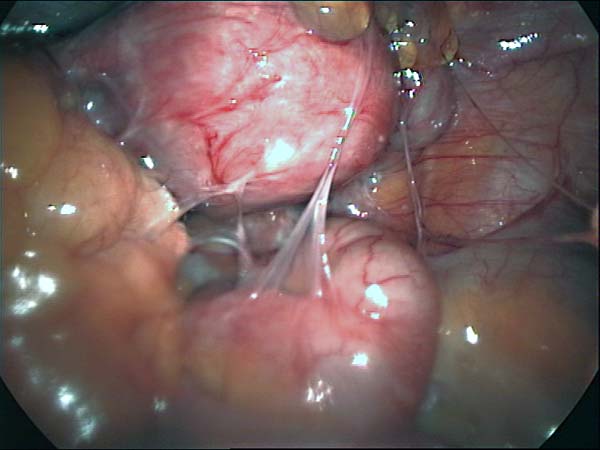

Photos laparoscopie Kyste ovarien Cystectomie ovarienne Septum utérin Grossesse tubaire